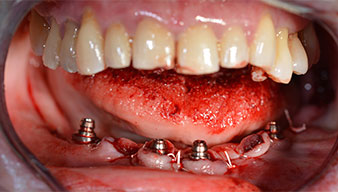

El siguiente ajuste programado es la propia inserción de los implantes. En nuestra clínica, solemos insertar los implantes con una fuerza de 32 Ncm de manera estándar (figs. 12 y 13).

El requisito imprescindible para el tratamiento inmediato es una alta estabilidad primaria. Para satisfacer dicho requisito, en este caso, se prescindió del corte de rosca. La unidad de accionamiento Implantmed de W&H empleada aquí, posee un modo propio para ello que también puede seleccionarse directamente y resulta imprescindible para muchas indicaciones. Los últimos giros para la inserción del implante superaron el valor de 32 Ncm, por lo que se realizaron manualmente. En tales casos, se recomienda utilizar la función autocortante de los implantes y girar el implante varias veces hacia delante y hacia atrás de forma que el implante se aproxime gradualmente hasta su posición definitiva sin ejercer una presión excesiva sobre el hueso (fig. 14).